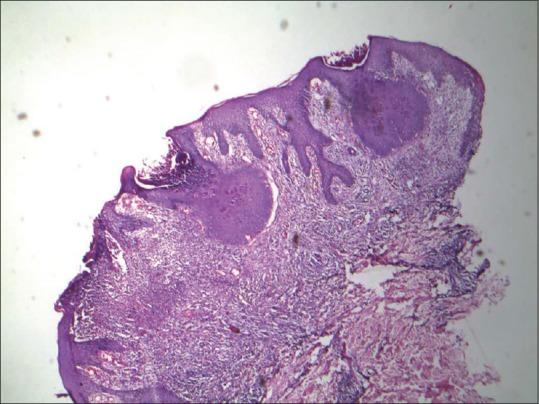

口服阿昔洛韦成功用于治疗眼部传染性软疣

Molluscum contagiosum is a common tropical contagious viral infection, involving the skin and the mucous membranes. Ophthalmic molluscum contagiosum is a relatively uncommon condition presenting as secondary follicular conjunctivitis or kerato-conjunctivitis and may present with or without obvious dermal skin lesions. Often, unsuspected and misdiagnosed by eye care providers or observed as a concomitant feature by a skin care provider, unilateral conjunctivitis due to molluscum contagiosum remains easily treatable. Clearance of the primary skin lesion leads to rapid and complete resolution of ophthalmic signs. Two cases of ophthalmic molluscum contagiosum treated successfully with oral antiviral drug acyclovir are presented herewith as anecdotal therapeutic evidence.

传染性软疣是一种常见的热带传染性病毒感染,累及皮肤和黏膜。眼部传染性软疣是一种相对不常见的病症,表现为继发性滤泡性结膜炎或角结膜炎,可能伴有或不伴有明显的皮肤病变。通常,眼部护理人员容易漏诊和误诊,或者皮肤科医生将其作为伴随特征观察到,由传染性软疣引起的单侧结膜炎仍然很容易治疗。原发性皮肤病变的清除会使眼部症状迅速完全消退。本文介绍了两例口服抗病毒药物阿昔洛韦成功治疗眼部传染性软疣的病例,作为轶事性治疗证据。